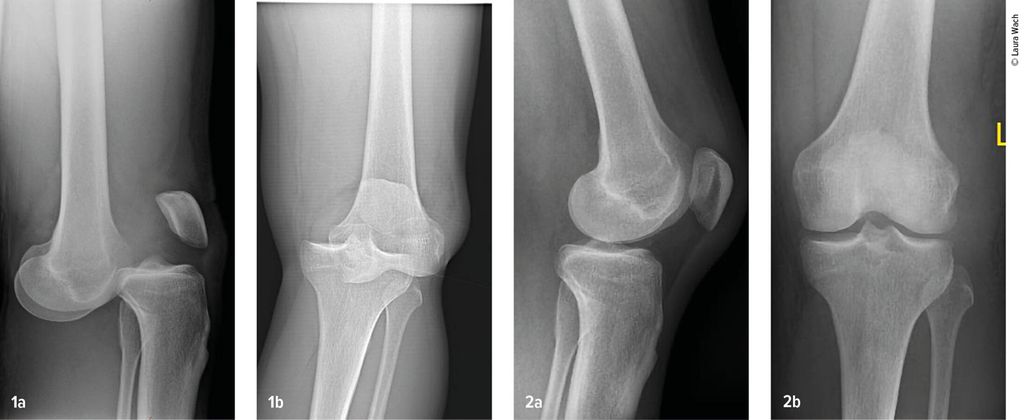

Gefäss- und Nervenverletzungen treten häufig im Zusammenhang mit einer Kniegelenkluxation auf. Henkelmann zitierte einen systematischen Review,3 der 23 Studien mit insgesamt 862 Patienten mit Kniegelenkluxationen umfasst. Bei 171 Patienten (18%) wurden Gefässverletzungen nachgewiesen. Diese kamen bei Patienten mit Schenck-Klassifikation vom Typ IIIL am häufigsten vor. Bei diesem Typ kommt es durch eine posteriore Kniegelenkluxation zur Ruptur beider Kreuzbänder und des lateralen Kollateralbandes (Abb.2 und 3). In 10 der Studien mit insgesamt 272 Patienten wurden auch Nervenverletzungen erfasst. 75 Patienten (25%) waren davon betroffen.

Abb. 2–3: Multiligamentverletzungen am jeweils linken Knie. (2) Klar ersichtlich, (3) leicht zu übersehen